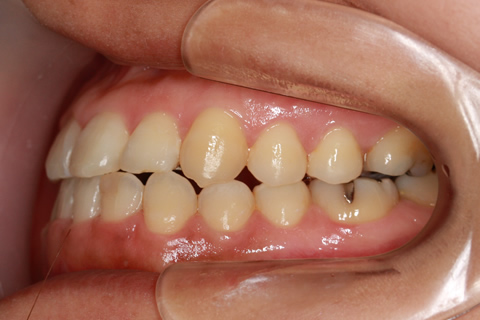

受け口(反対咬合)の症例

症例一覧